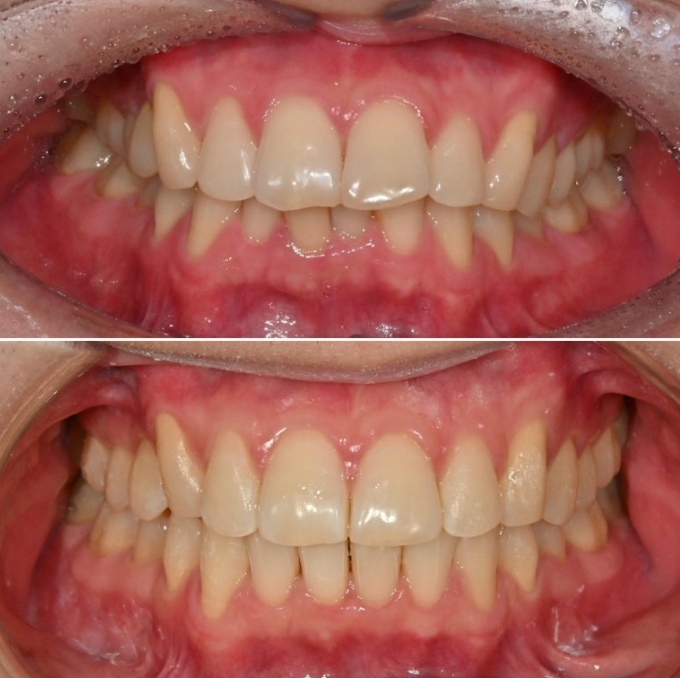

이제 전후 비교 보겠습니다.

25.02~25.12

과개교합의 개선으로 아래앞니가 온전히 보이게 되었습니다.

윗니 뻗침으로 인해 위 아래 간격이 크면 아랫입술이 그 사이로 숨습니다.

그래서 초진 아랫입술이 얇아보이는 거죠.

교정 후 위아래 간격이 줄면서 아랫입술이 제 모습을 드러냈습니다.

드라마틱한 돌출 해소는 포기한 간단한 인비절라인 라이트 교정이지만, 앞니 뻗침이라도 해결되니 미소가 한층 깔끔합니다.